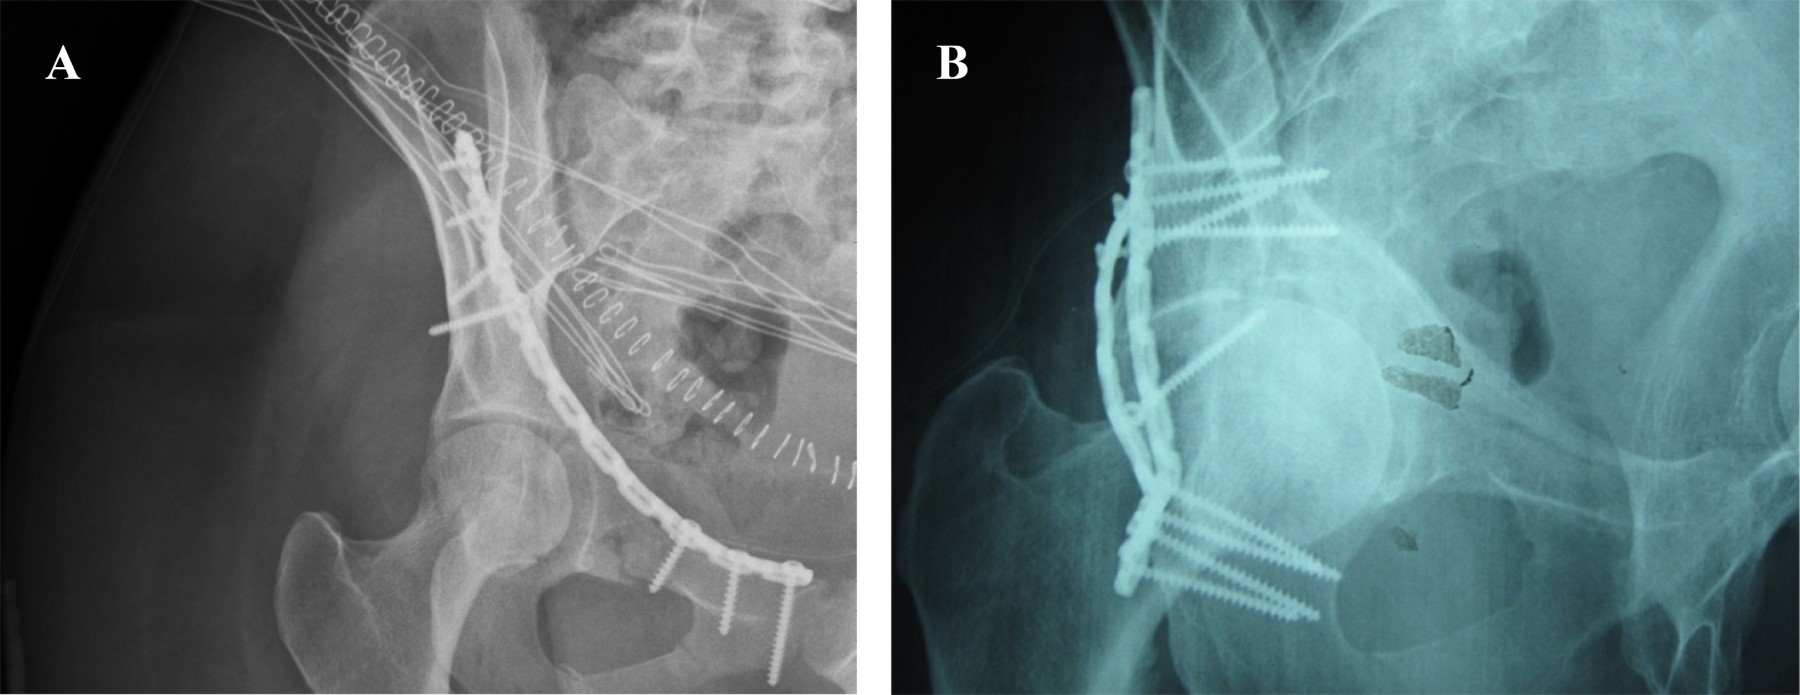

La reducción postquirúrgica de la fractura está asociada al desarrollo de coxartrosis (Figura 1). En todos aquellos pacientes con un desplazamiento postquirúrgico mayor de 2 mm, donde no se consiguió durante la cirugía una reducción anatómica de la fractura debido a la complejidad de la misma, hubo degeneración artrósica de la articulación (p = 0.001).

Figura 1